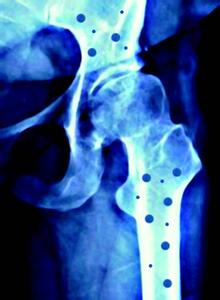

活体骨是一种有生命的器官,中文字幕麻豆厂家分析骨具有新陈代谢以及生长、发育的特点,并有破坏、重建和创伤愈合、修复再生的能力。骨不是固定不变的,在不同的年龄有不同的表现。

人体正常的骨代谢过程是骨组织不断进行改建活动的一个复杂的过程,包括骨吸收和骨形成两个方面。该过程的顺序一般认为是:激活——骨吸收——骨形成。首先,参与骨吸收的破骨细胞大量被激活,破骨细胞将骨基质溶解,并把骨中的钙移出,形成骨吸收;随后在骨吸收的表面排列成骨细胞,成骨细胞合成非矿化的骨基质,同时把钙运至钙化区;最后,钙、磷结晶逐渐沉积在骨基质中,骨基质钙化,形成骨组织。在骨的代谢过程中,每天都有一定量的骨组织被吸收,又有相当数量的骨组织合成,两者保持着动态的平衡。当骨吸收大于骨质形成,可出现骨丢失、发生骨质疏松症、骨软化病等症。当骨形成而无相应的骨吸收时,则可出现骨质硬化。

骨的代谢过程受到体内许多因素的调节,钙、磷、镁、内分泌激素、维生素等多种因素均起着至关重要的作用。当这些因素的代谢发生异常时,就可造成骨代谢的紊乱。

中文字幕麻豆分析尤其是钙,钙是人体中含量最多的矿物质元素,在人体内含量仅次于氧、碳、氢、氮,约占人体重量的2.0%。一个正常成年人体内钙的总含量约为1千克。在血浆和细胞外液中约有1克,其余均以磷酸盐、碳酸盐和氢氧化物的形式存在于骨骼和牙齿中。因此,人们形象地把骨骼看成人体存放钙的仓库。